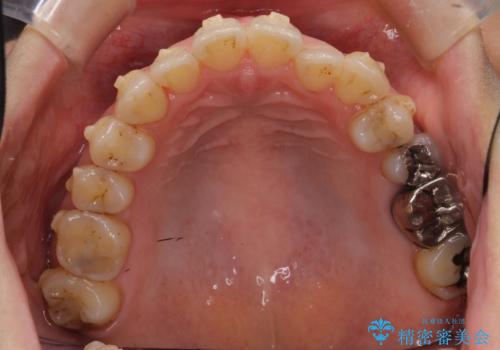

- 前歯のガタガタを主訴に来院。

前歯は開咬傾向であり、小臼歯から大臼歯にかけてもオーバージェットは非常に小さく咬耗していました。

非抜歯で前歯の重なりを作るのは難しいとご説明しましたが、インビザラインでできるところまで並べていくことになりました。

途中再評価を行い、矯正用のミニスクリューを用いて奥歯を遠心移動し、前歯の出っ歯傾向を改善しました。

左上12の段差についてはここまで直すのにもかなり時間がかかりました。インビザライン単独では限界があると説明し、ワイヤーの部分矯正もご提案しましたが、患者様のご希望によりインビザラインでできるところまで頑張るということで4回ほどリファインメントを行いました。